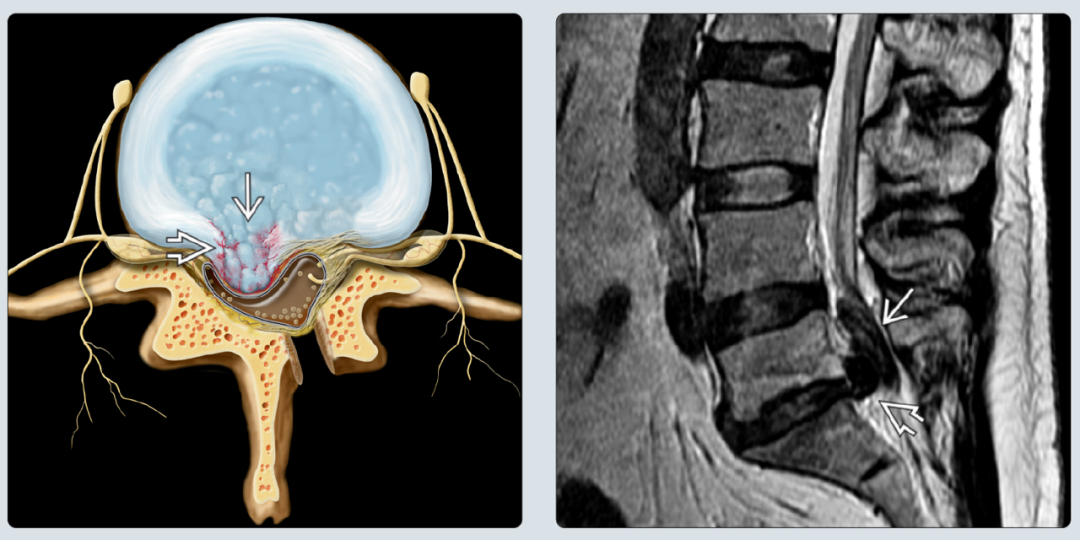

日常生活当中积累性的损伤造成腰椎间盘结构受损,最终导致腰椎间盘突出。千万不要小看平时一些细微的动作。比如说搬东西的时候扭了腰,反复弯腰、打高尔夫球、蹲着工作、甚至是长期的开车,都可能会对腰椎间盘造成细微的损伤。长期的细微损伤不断积累,会在腰椎间盘外层的纤维环上留下一些裂隙。这时候椎间盘内部的髓核组织会在压力的情况之下,从这些细小的损伤裂隙逐渐的突出。有的时候神经末梢甚至可能会从这些微小的缝隙当中长入到椎间盘当中,造成了慢性的腰疼。长期的积累性的损伤不断的破坏了椎间盘外侧的纤维环的结构,同时使腰椎间盘内部的髓核组织也向外突出,突出的程度逐渐加重,最终造成了对椎管内的神经根的压迫,从而产生了腰腿疼的症状。

(图片选自image in spine surgery)